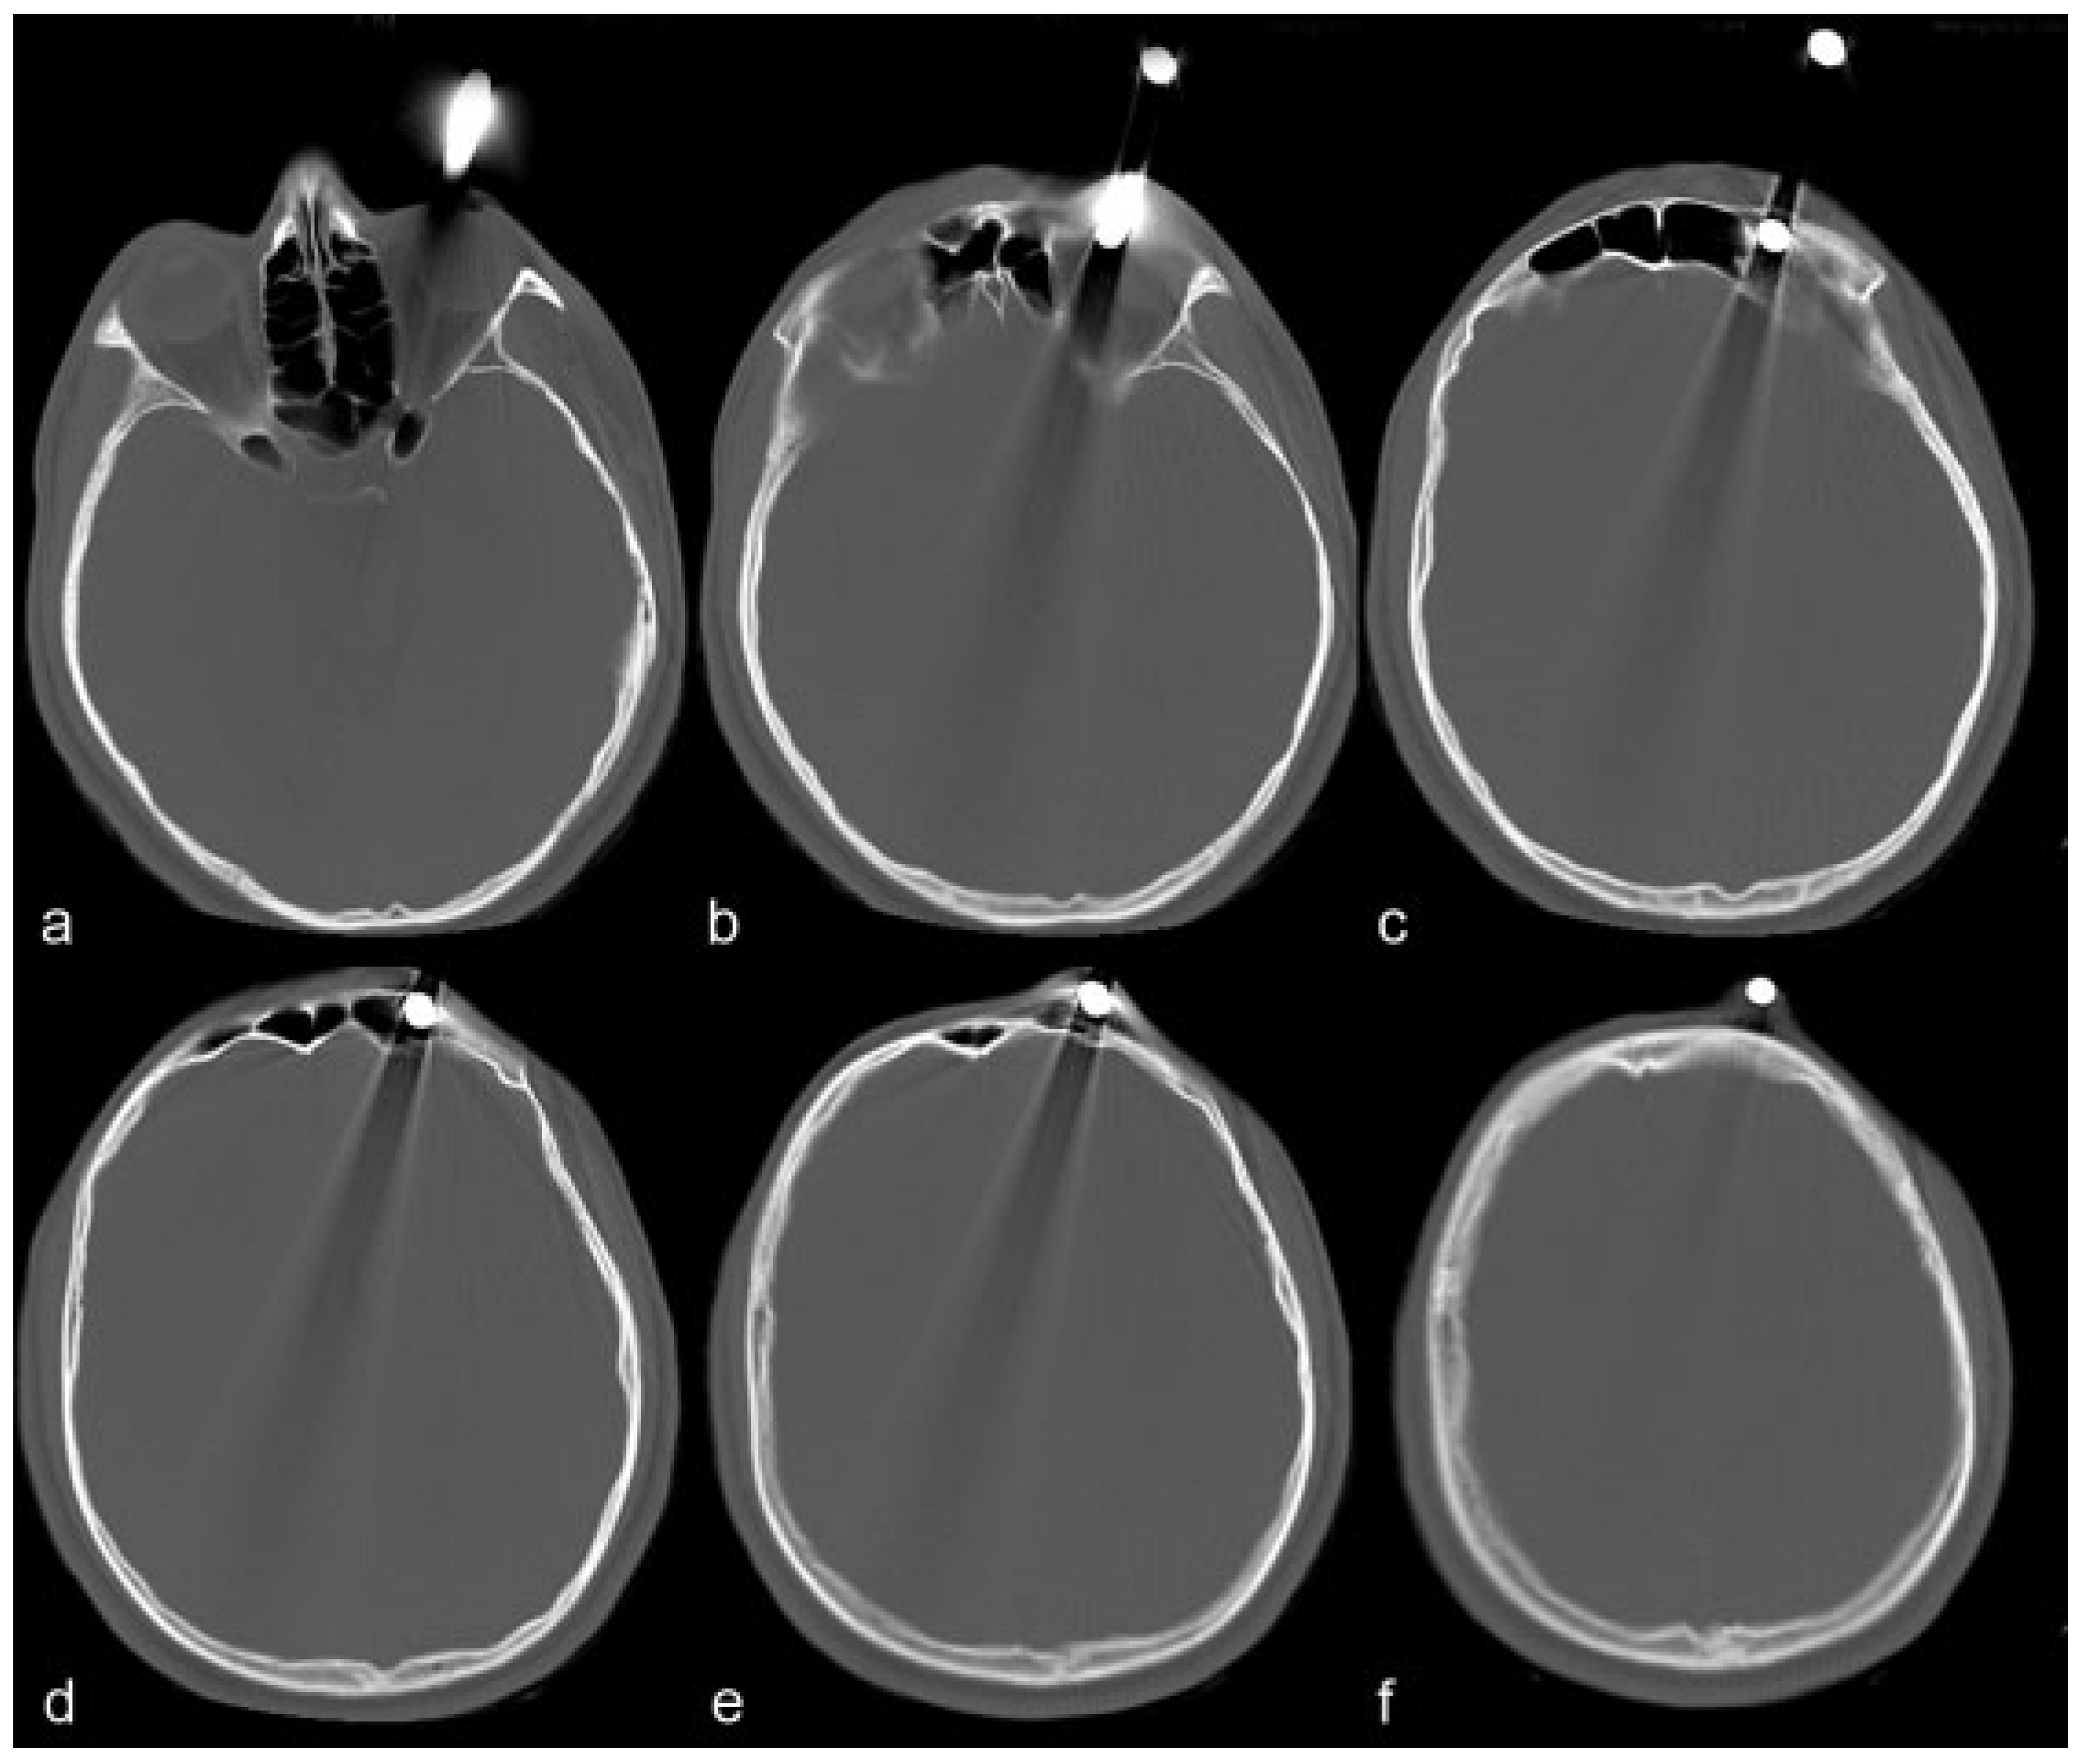

Transorbital Orbitocranial Penetrating Injury with an Iron Rod

:Case Report